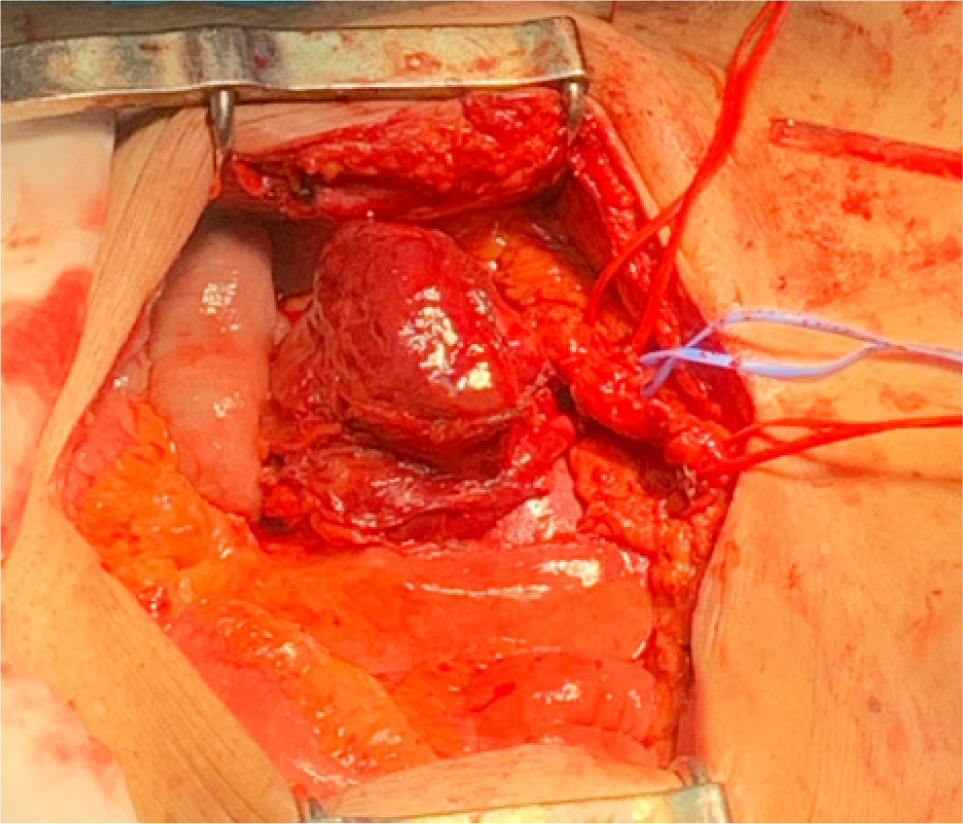

Bilateral RP and ureteric catheterization were first performed for the identification of the hila and calyces of the HSK (Figures 4 & 5). A lower midline laparotomy was performed. The tumor was identified, measuring 7 cm in diameter (Figure 6). Careful dissection of complex hilar structure was performed. Two renal arteries and two renal veins supplying the right side were identified and slung (Figure 7). The tumor was resected with artery clamping (Figure 8). The right lateral calyx of the pelvicalyceal (PC) system was involved and resected. The PC system was closed with 3/O PDS. Renorrhaphy was completed with 3/O V-Loc, and parenchyma was closed with 2/O V-Loc. Ischemic time was 20 minutes, and total operation time was 332 minutes. Blood loss was 420 mL. The patient had completed 1 week of levofloxacin and was discharged on postoperative day 6 with one kick of fever that spontaneously subsided.

Figure 7: Carefully slung vasculatures.

Figure 8: Resected tumor.